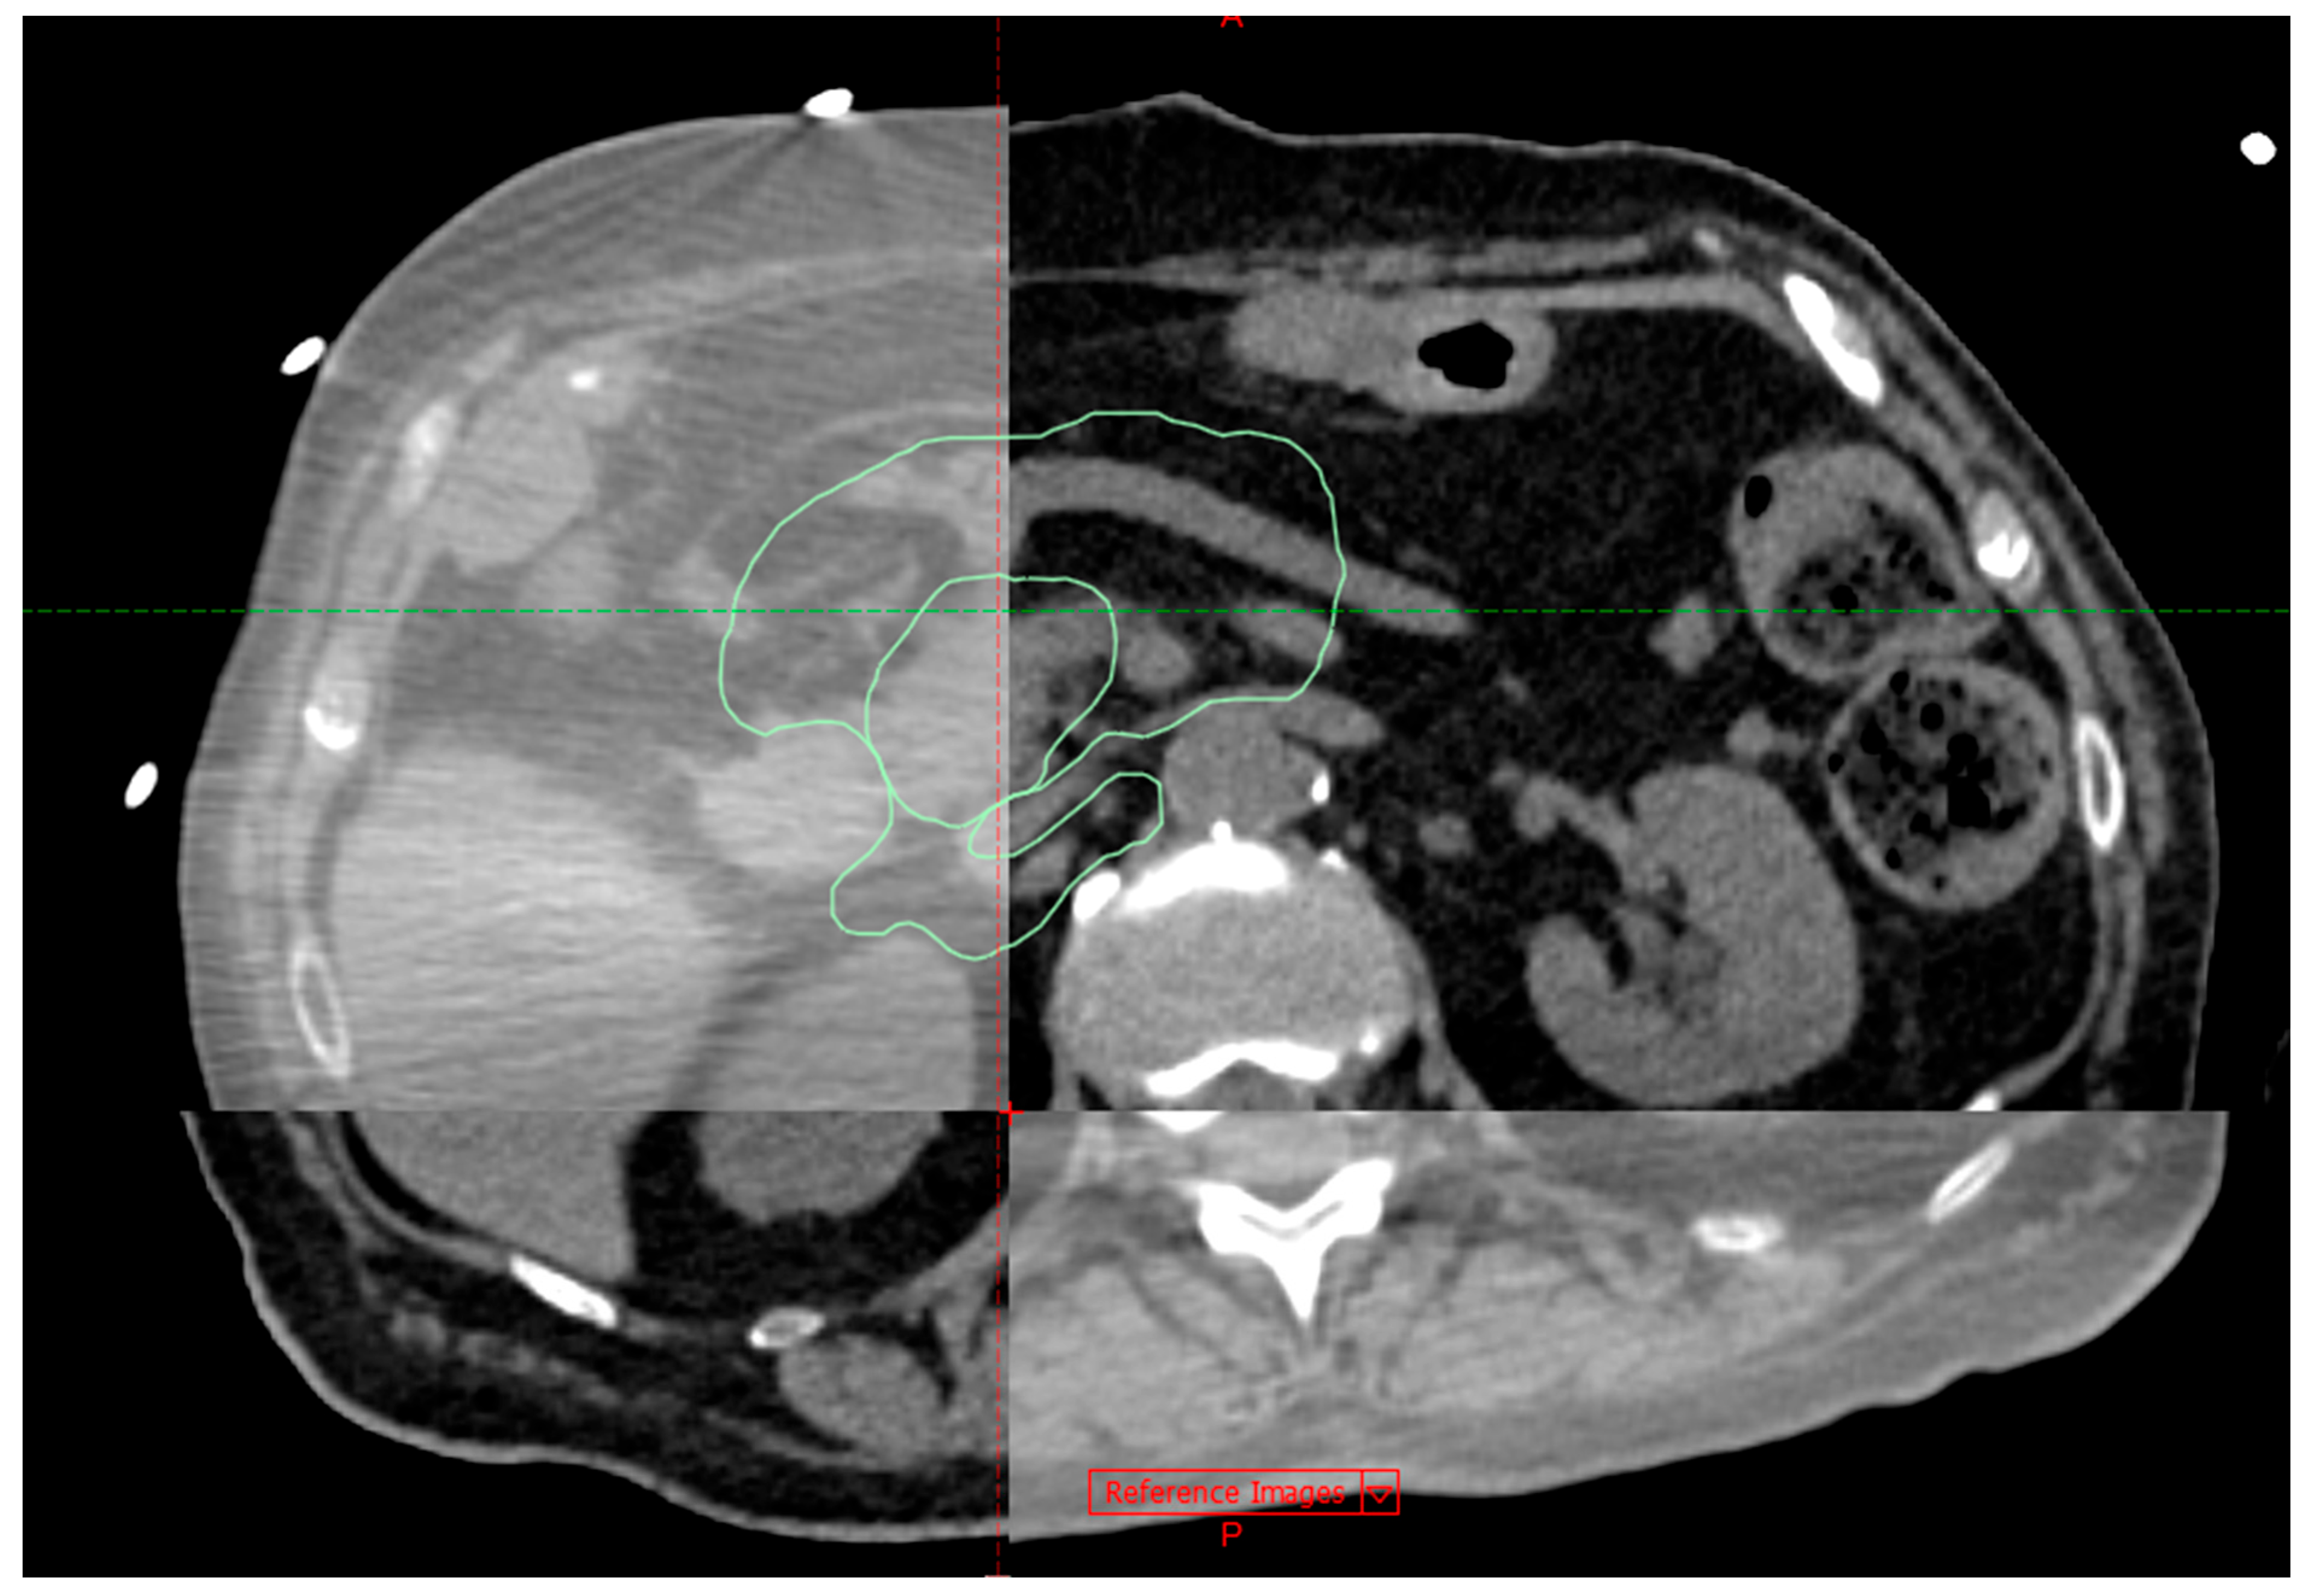

2.6. Stereotactic Ablative Radiotherapy

- The mean dose to the SIB-PTV was considerably higher than the prescription dose;

- No planning constraints on the dose maximums were set as long as they were inside the SIB-PTV;

- The optimisation of the dose distribution was performed with the purpose of achieving a required target coverage of V (98–99.5%) = 80% of the prescribed dose for the SIB-PTV.

- Σ = 0.4 mm, as determined by end-to-end tests; for systemic error;

- σ = 2 mm, defined as gating windows; for random error.

- 1.

- Primary (directly adjacent to pancreas and highly radiosensitive) OARs: stomach, duodenum, small bowel;

- 2.

- Other OARs: liver, great vessels, spinal cord, kidneys.